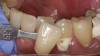

Case Study 2

A 45-year old male patient presented with tooth No. 21 that had an intermediate restorative material (IRM) restoration on the facial aspect after a pulpotomy due to a carious lesion into the pulp from the facial (Figure 7 and Figure 8). The patient had root canal therapy and a post-and-core buildup placed on No. 21 before the crown. The patient was involved in the decision-making for the enamel shade on No. 21. He wanted to make sure that the clinicians did not match No. 21 with No. 20 because he felt the shade on No. 20 was too dark. Instead, the patient wanted to match the new ZLS that had been planned on No. 21 with the natural shade of No. 23 and No. 24. The facial and occlusal views revealed the obvious differences in shade between No. 21 and No. 20. The plan was to use pressable ZLS due to its esthetics, shade-matching abilities, strength, and ease of finishing, so it was decided to involve the dental laboratory technician with the shade-taking process. In planning the discussion with the laboratory technician, the author felt that the best shade would be a Vita A3.5. However, because the laboratory technician worked about 90 minutes away, the author wanted to get his input on the shade by sending him several photographs using the shade the author felt tooth No. 21 was (ie, Vita A3.5) plus shades that were close (ie, Vita A3 and Vita A4). Laboratory technicians are more familiar with shading techniques and may see something that the dentist did not see in the surrounding teeth. This is important when using ZLS to take full advantage of the blending ability that this material displays. The final crown displayed a vibrant match of hue and chroma (Figure 9 through Figure 13).